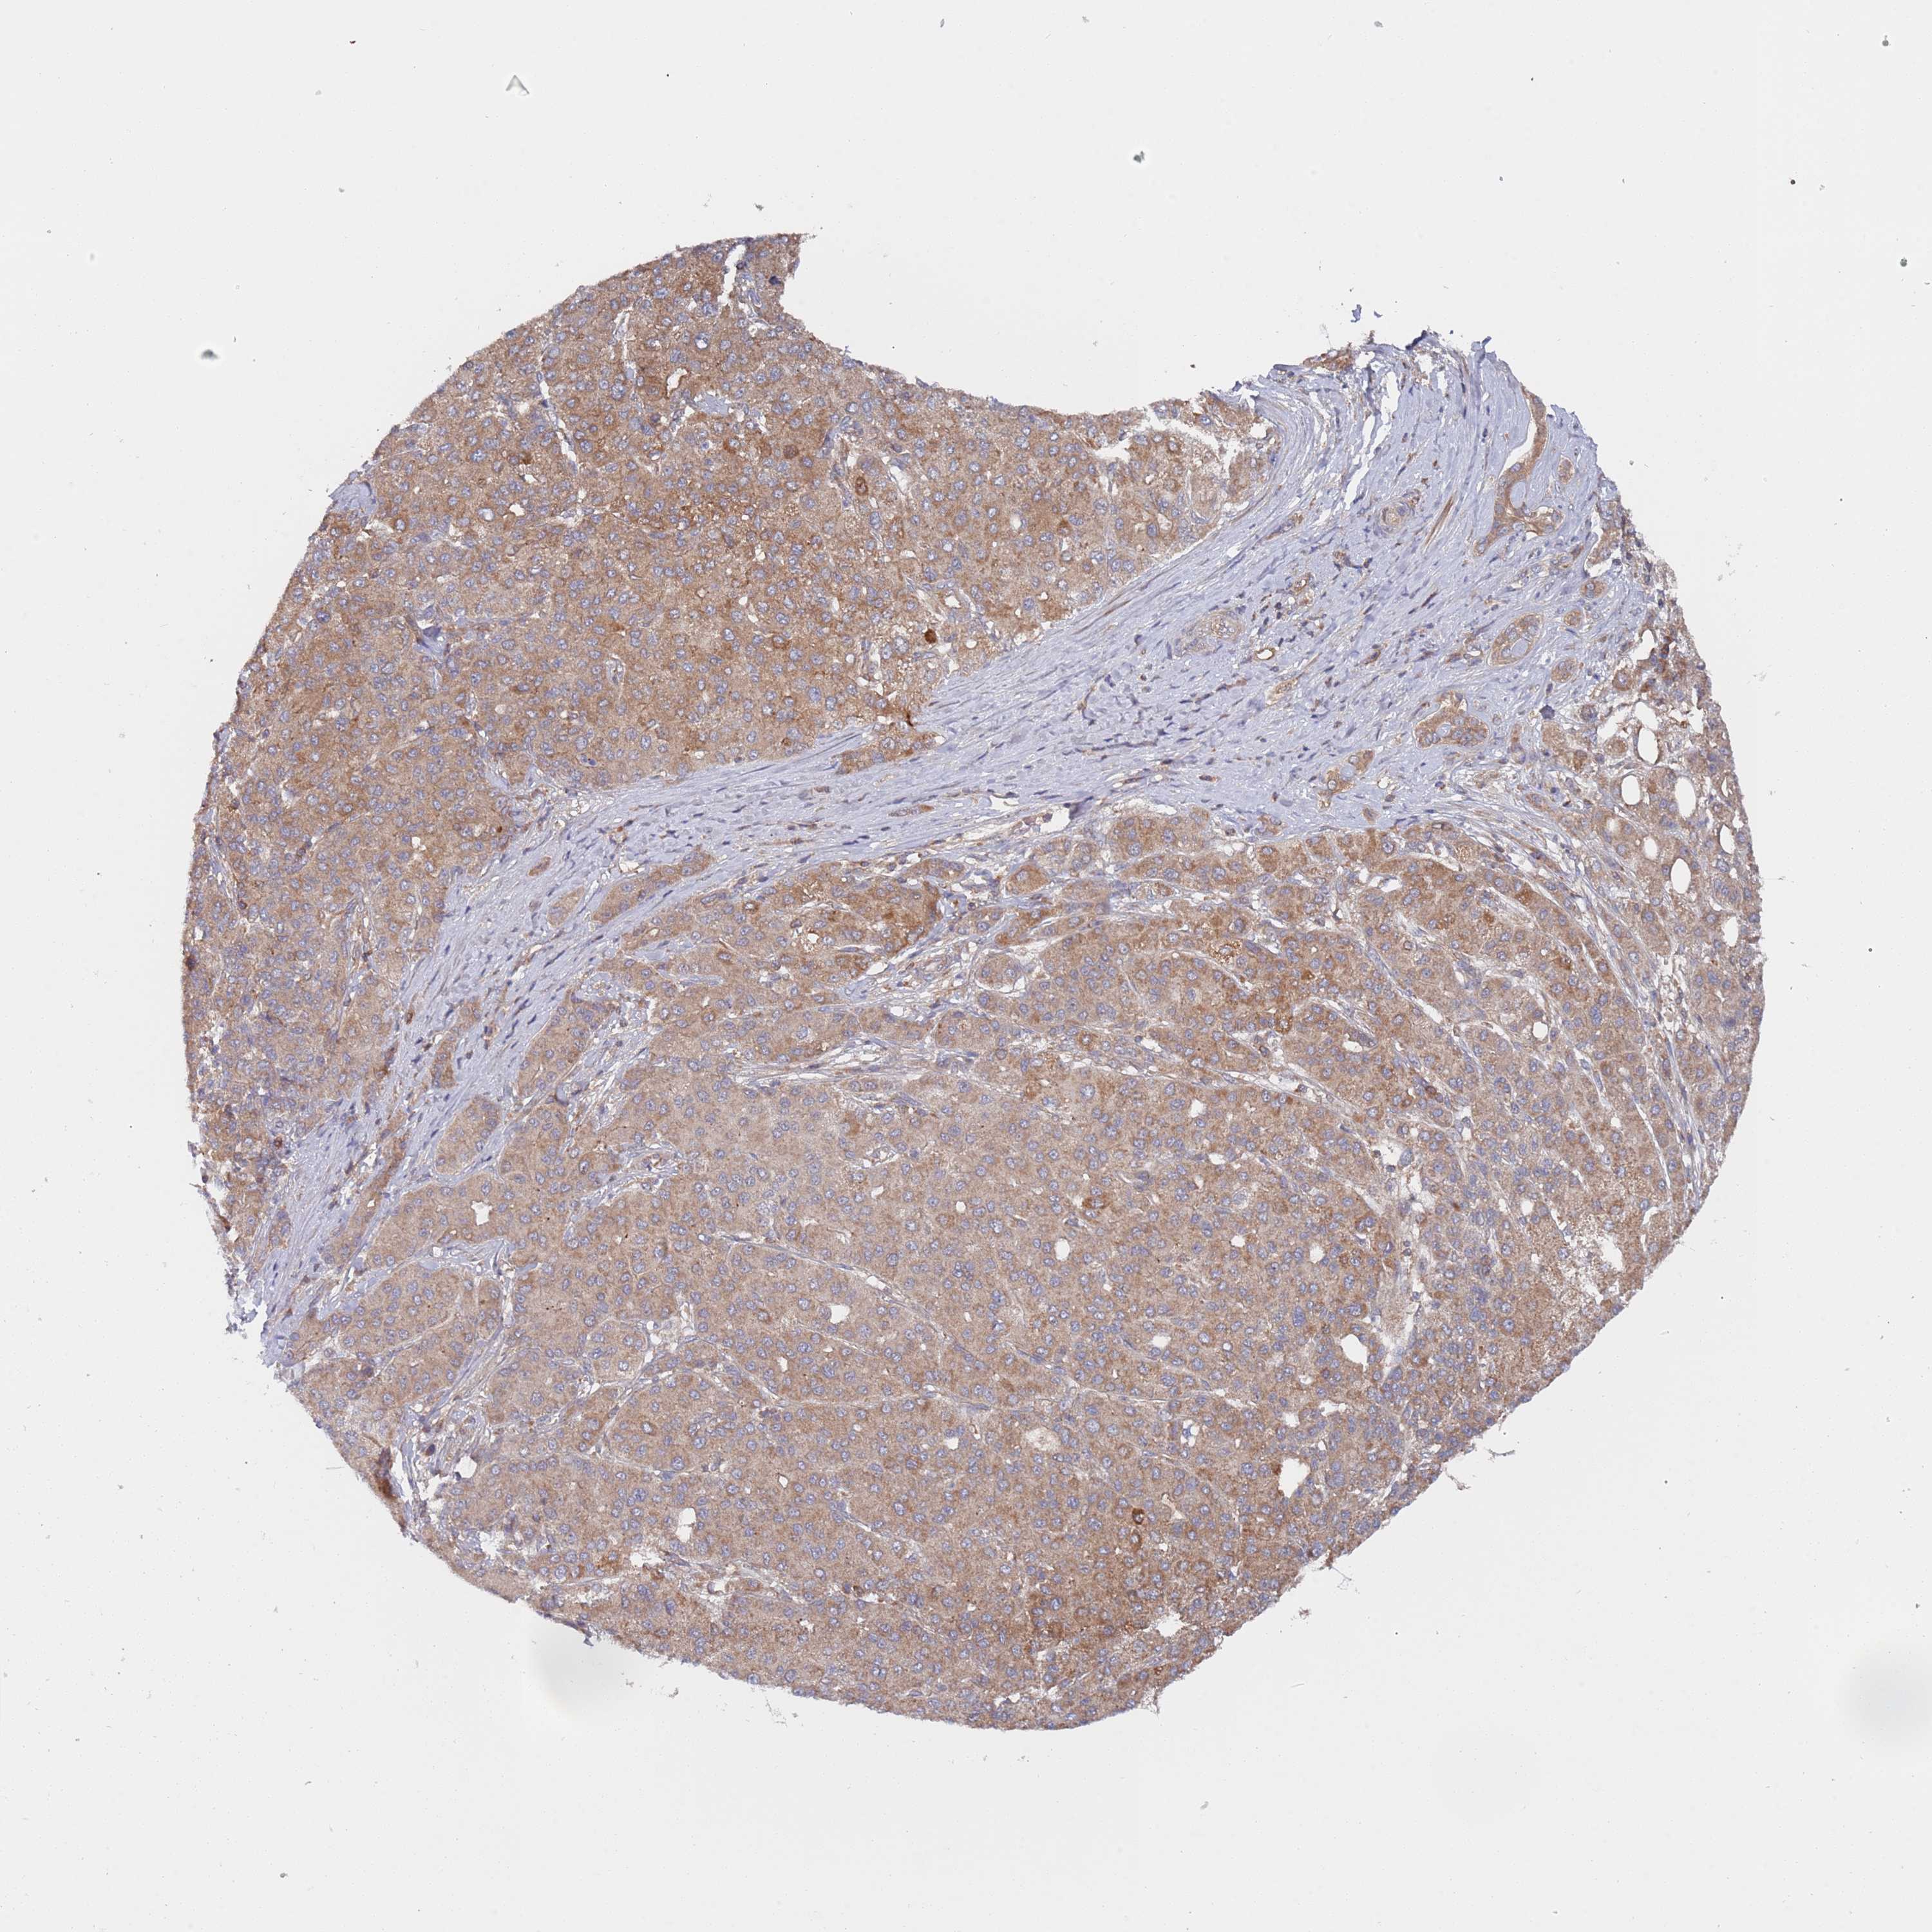

LIVER CANCER - Protein expressioni

A mouse-over function shows sample information and annotation data. Click on an image to view it in a full screen mode. Samples can be filtered based on level of antibody staining by selecting one or several of the following categories: high, medium, low and not detected. The assay and annotation is described here.

Note that samples used for immunohistochemistry by the Human Protein Atlas do not correspond to samples in the TCGA dataset.

Antibody stainingi

Antibody staining in the annotated cell types in the current human tissue is reported as not detected, low, medium, or high, based on conventional immunohistochemistry profiling in selected tissues. This score is based on the combination of the staining intensity and fraction of stained cells.

Each image is clickable and will lead to virtual microscopy that enables deeper exploration of all samples and also displays staining intensity scores, fraction scores and subcellular localization as well as patient and tissue information for each sample.

Antibody HPA046952

Staining

High

Medium

Low

Not detected

Intensity

Strong

Moderate

Weak

Negative

Quantity

>75%

75%-25%

<25%

None

Location

Nuclear

Cytoplasmic/membranous

Cytoplasmic/membranous,nuclear

Cholangiocarcinoma

Carcinoma, Hepatocellular, NOS